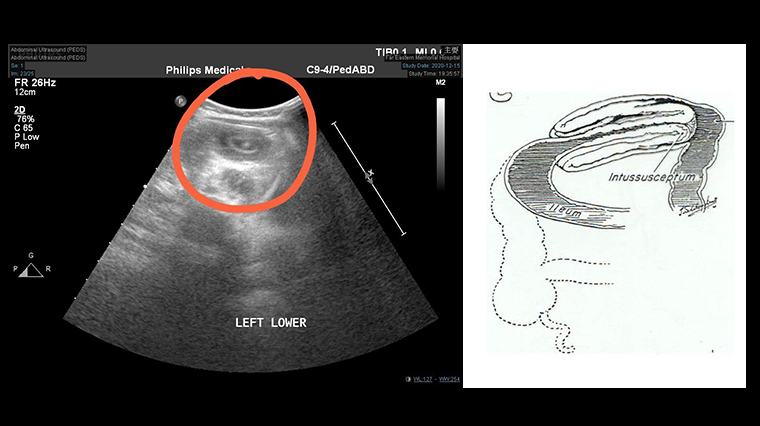

小兒科醫師立即做腹部超音波檢查,發現影像有一大段標靶似的圖形,甜甜圈似的影像,由此確診為「腸套疊」。醫生更發現腸子套到降結腸,緊急會診小兒外科,經腹腔鏡手術將腸套疊的腸子復位,經過2天休養及拉肚子症狀好轉,才順利出院回家。

▲經腹部超音波檢查,可清楚看見標靶似的圖形(如右圖),即是「腸套疊」。(圖/亞東醫院提供)

腸套疊(Intussusception)是小兒專科常見的腹部急症之一。亞東紀念醫院小兒外科主治醫師許琪琪表示,幼兒型的腸套疊多為迴腸套入結腸型,腸套疊時的腸子像是天文望遠鏡收起來一樣,近端腸子套入遠端,造成腸子阻塞。